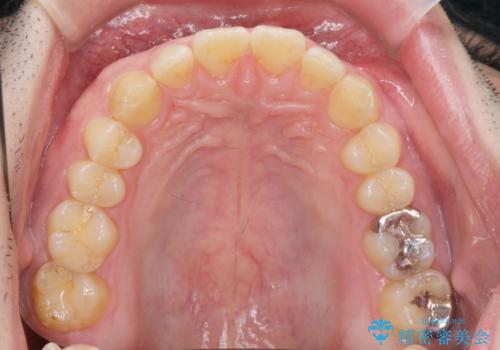

ディープバイトのマウスピース矯正

- 飛び出してしまい、隙間のある前歯をきれいに並べたい、と矯正治療を希望され来院されました。

上顎前歯を後方に引き、隙間を閉じるためには下顎前歯の絶対的な圧下を行い、深い噛み合わせを改善することが必要です。

前歯でチューイーをしっかり噛み、咬合圧を伝えたことで下顎前歯が圧下し、上顎前歯の隙間を閉じることができました。